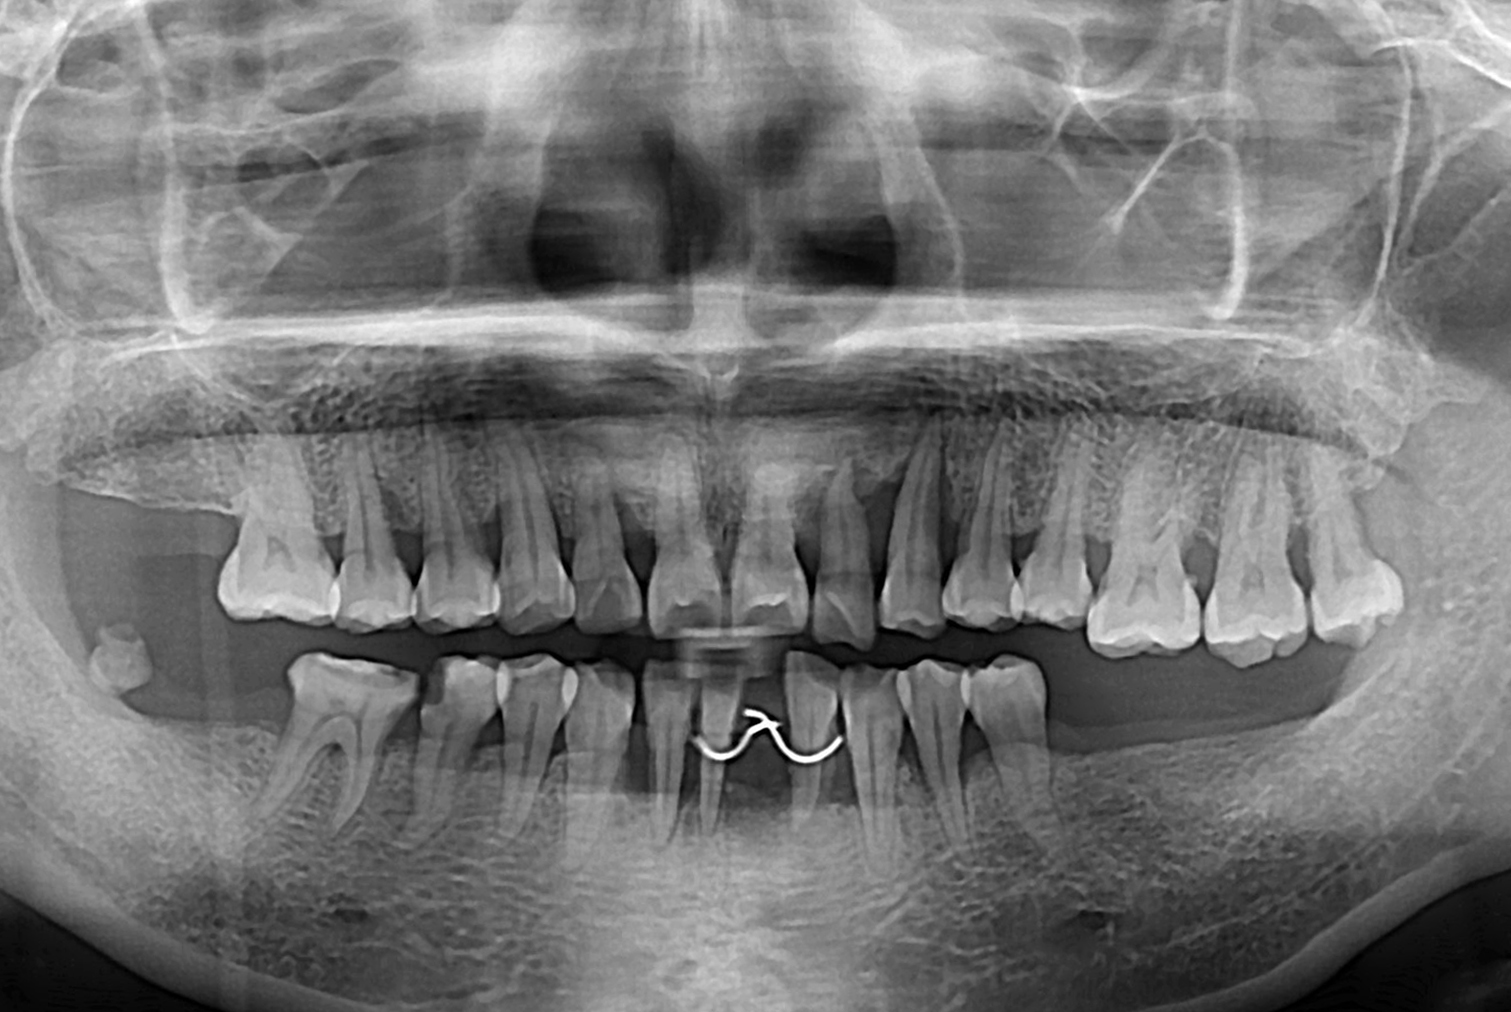

7dab08e6191af6418c91e1b24317b2c5.jpg

치료전 : 2019-03-21